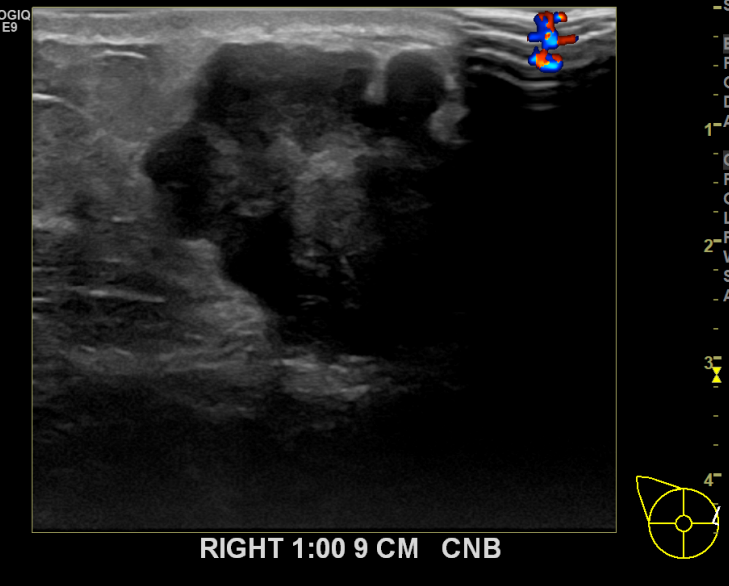

상기환자 외부검사상 이상 소견으로 내원하신 60대 여성분으로 우측의 의심스러운 혹 조직검사 후 유방암 진단 되었습니다. 빠른 쾌유를 기원합니다